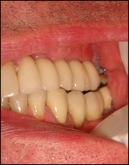

Après quatre à 6 mois l’os est complètement soudé et les implants peuvent être posés.

Photos implants dans greffe osseuse